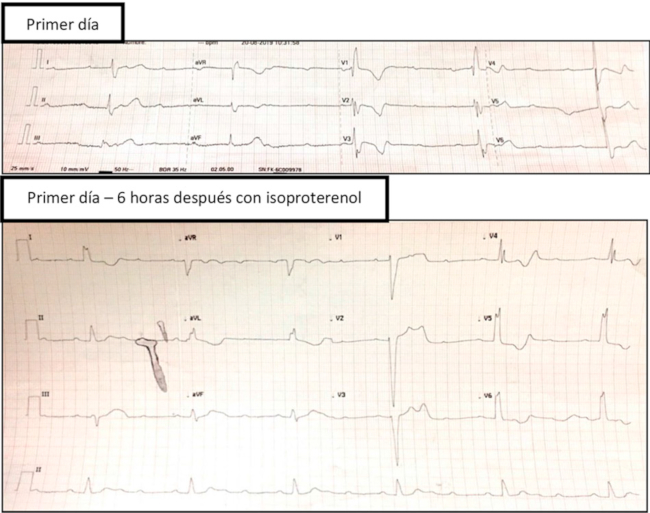

Presentamos el caso de un hombre de 26 años, sin antecedentes de relevancia, que ingresa tras una caída de motocicleta por colisión frontal con un auto. Este sujeto presentaba politraumatismo con trauma torácico cerrado y de antebrazo derecho, con posterior pérdida de la conciencia, y traumatismo encefalocraneano. Al ingreso a la institución se realiza ECG, este evidencia bloqueo aurículo-ventricular (BAV) completo e imagen de bloqueo completo de rama derecha BCRD, a una frecuencia cardíaca (FC) de 25 lpm (Fig. 1a). Al examen físico, el paciente se encontraba lúcido, normotenso, sin foco neurológico y con una fractura expuesta del antebrazo derecho (Gustilo I). A los pocos minutos desarrolla BAV 3:1 con conducción con BCRI, que el paciente no tenía en un electrocardiograma del año anterior. Se medica con isoproterenol y aumenta la FC a 60 lpm (Fig. 1b). Se realiza ecocardiograma de urgencia, que fue normal. En el laboratorio de ingreso se observa elevación de troponina I:2,16 UI/L(valor normal <0,02 UI/L). El paciente presentó Bloqueo aurículo-ventricular completo (BAVC ) y BCRI durante las primeras 24 horas de internación y se encontraba asintomático; luego comenzó a alternar períodos de ritmo sinusal con depresión sinusal, manteniendo el BCRI. En los estudios realizados por el politraumatismo no se evidenciaron fracturas costales, pero sí una imagen de contusión pulmonar y derrame pleural derecho en la tomografía de tórax, y fractura distal de radio-cúbito. A las 24 h del ingreso se repitió un ecocardiograma, que evidenció hipertrofia del VI (SIV de 1,3 mm y PP de 1,1 mm), con movimiento anormal del septum (por BCRI). Se realizó resonancia cardíaca para evaluar la presencia de edema, hematoma o fibrosis que justificara el trastorno del ritmo; el resultado fue normal. Hacia el cuarto día del accidente vial, el paciente se estabilizó en ritmo sinusal, con una FC de 55 lpm, pero persistió con BCRI, y, dado que debía ser operado por la fractura del brazo, se indicó la realización de un estudio electrofisiológico al día 14 posaccidente. Dicho estudio mostró una conducción AV normal, con HV prolongado, de 80 milisegundos, en el contexto del BCRI. Se le colocó un marcapasos transitorio para la cirugía. En el seguimiento a seis meses, persiste con BCRI y asintomático.